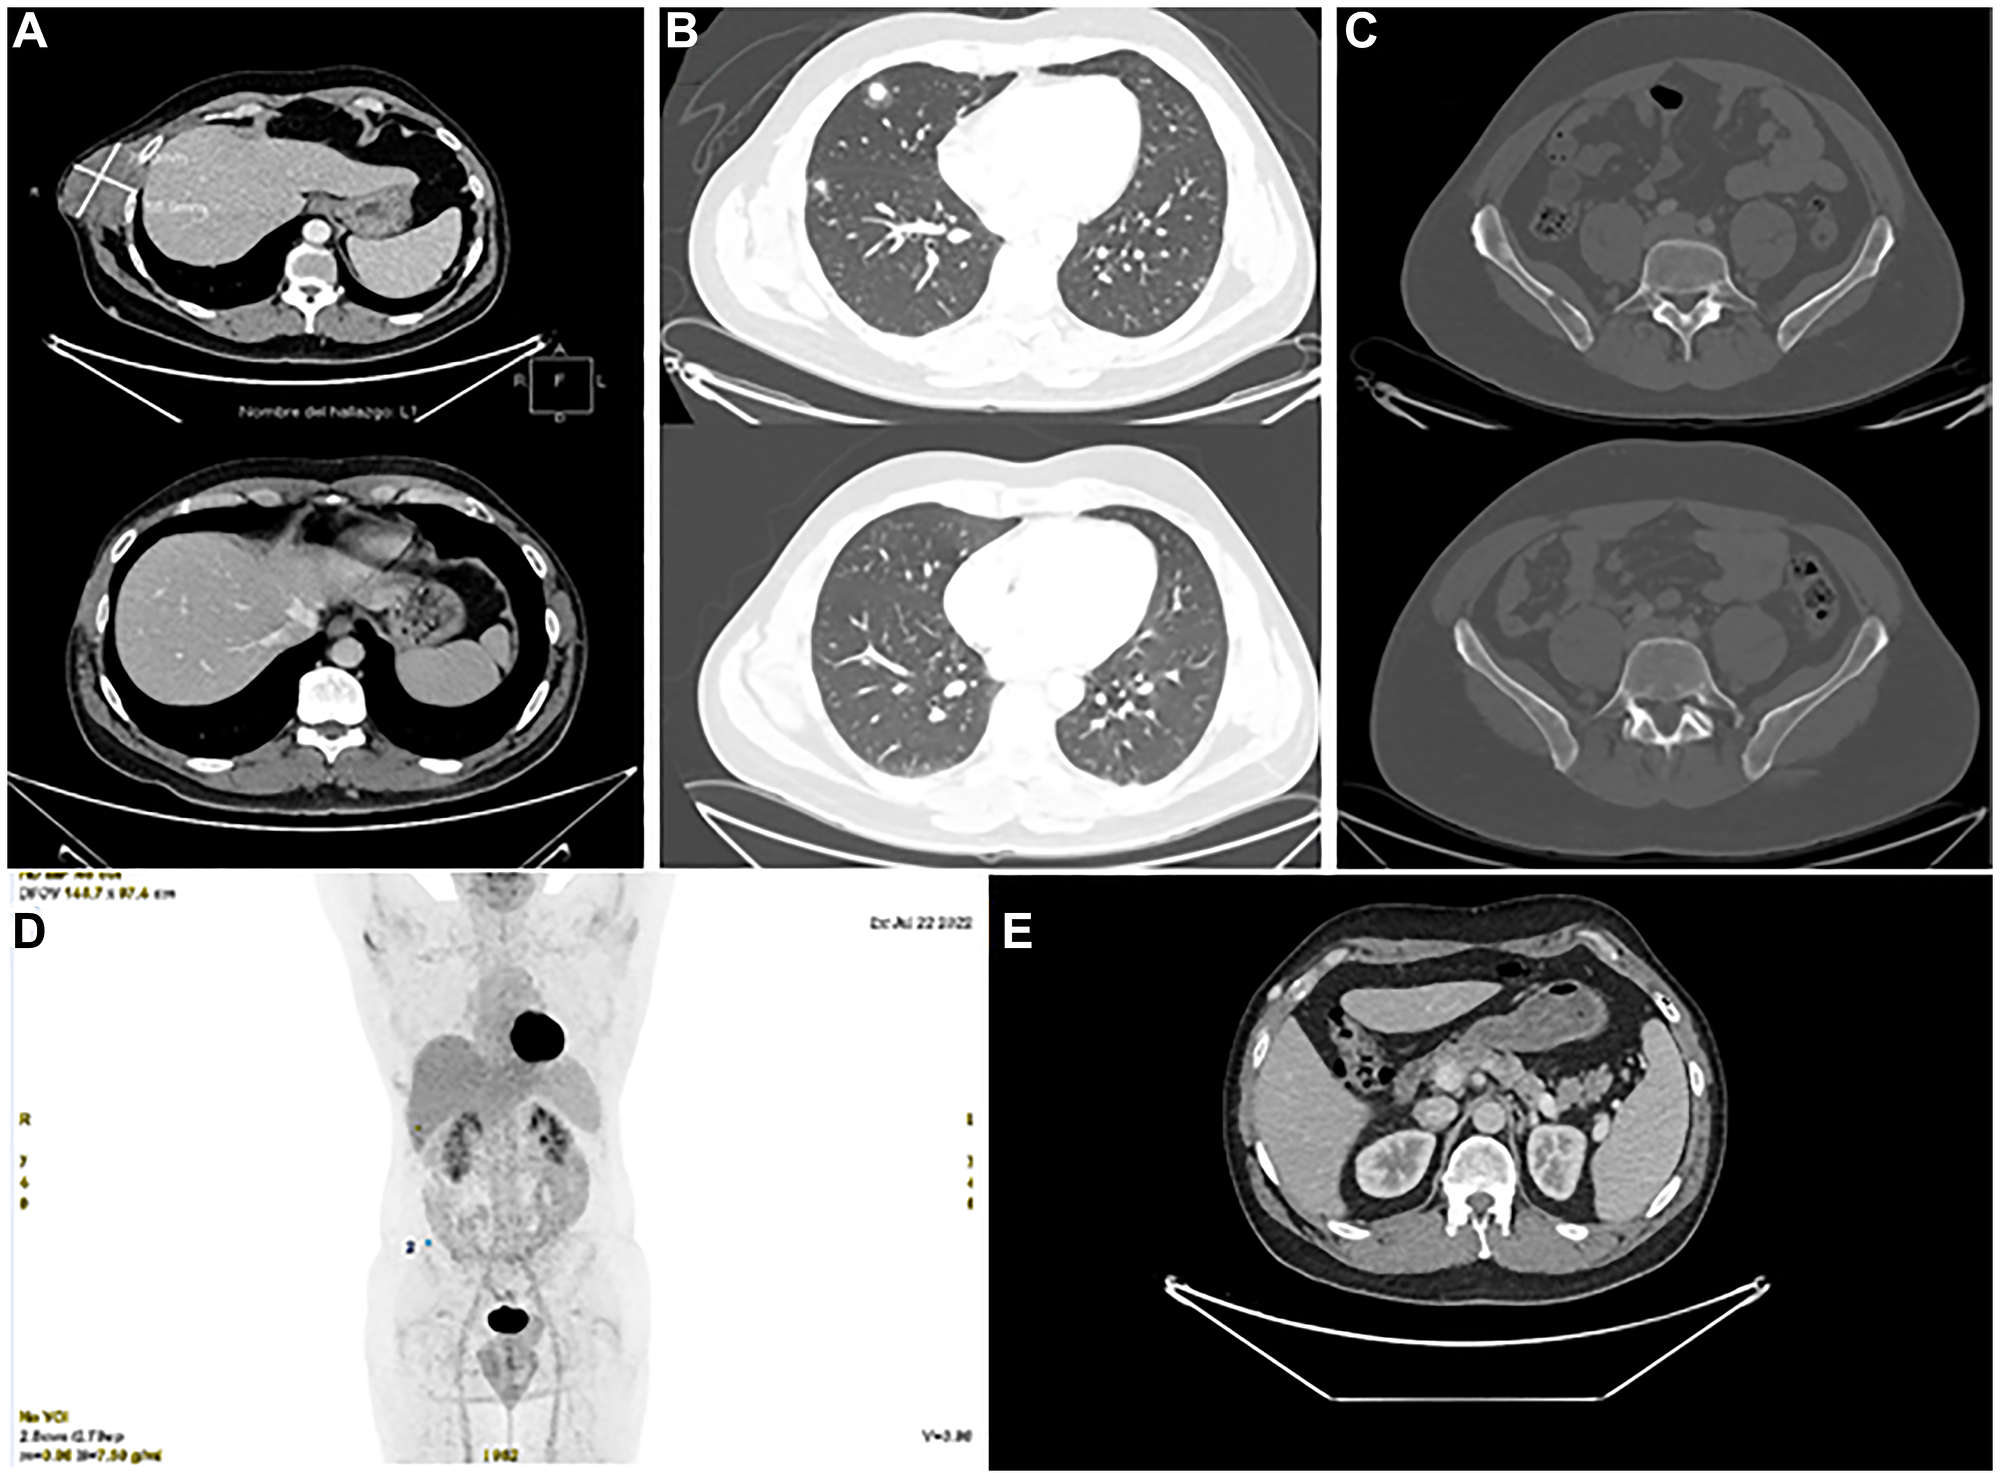

At the most recent follow-up in August 2024, the patient remains on a complete metabolic and radiologic response for more than two years since encorafenib plus binimetinib was started (Figure 5). The patient has neither presented any treatment-related side effects nor has required dose interruption or modification, and remains completely asymptomatic.

Figure 5: Radiological evolution after targeted therapy.

Comparison of CT scans with intravenous contrast, baseline vs. after 6 months of treatment (AC) and metabolic complete response on CT-PET (D). (A) Complete radiological response of right costal mass, persistence of benign hypervascular component. (B) Complete radiological response of metastatic pulmonary nodules. (C) Complete radiologic response of right iliac lesion. (D) Metabolic complete response in CT–PET 07/20/2022. (E) Persistence of benign hypervascular subcutaneous, intermuscular and intramuscular nodules adjacent to the primary tumor in the right lateral abdominal wall.